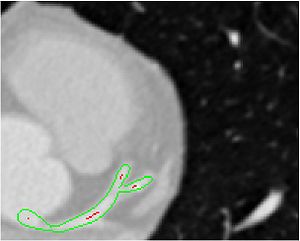

• Slice-wise visualization of vessel segmentation Slice-wise view of vessel segmentation result: segmentation result (green) and extracted center-line (red) superimposed on CTA image data